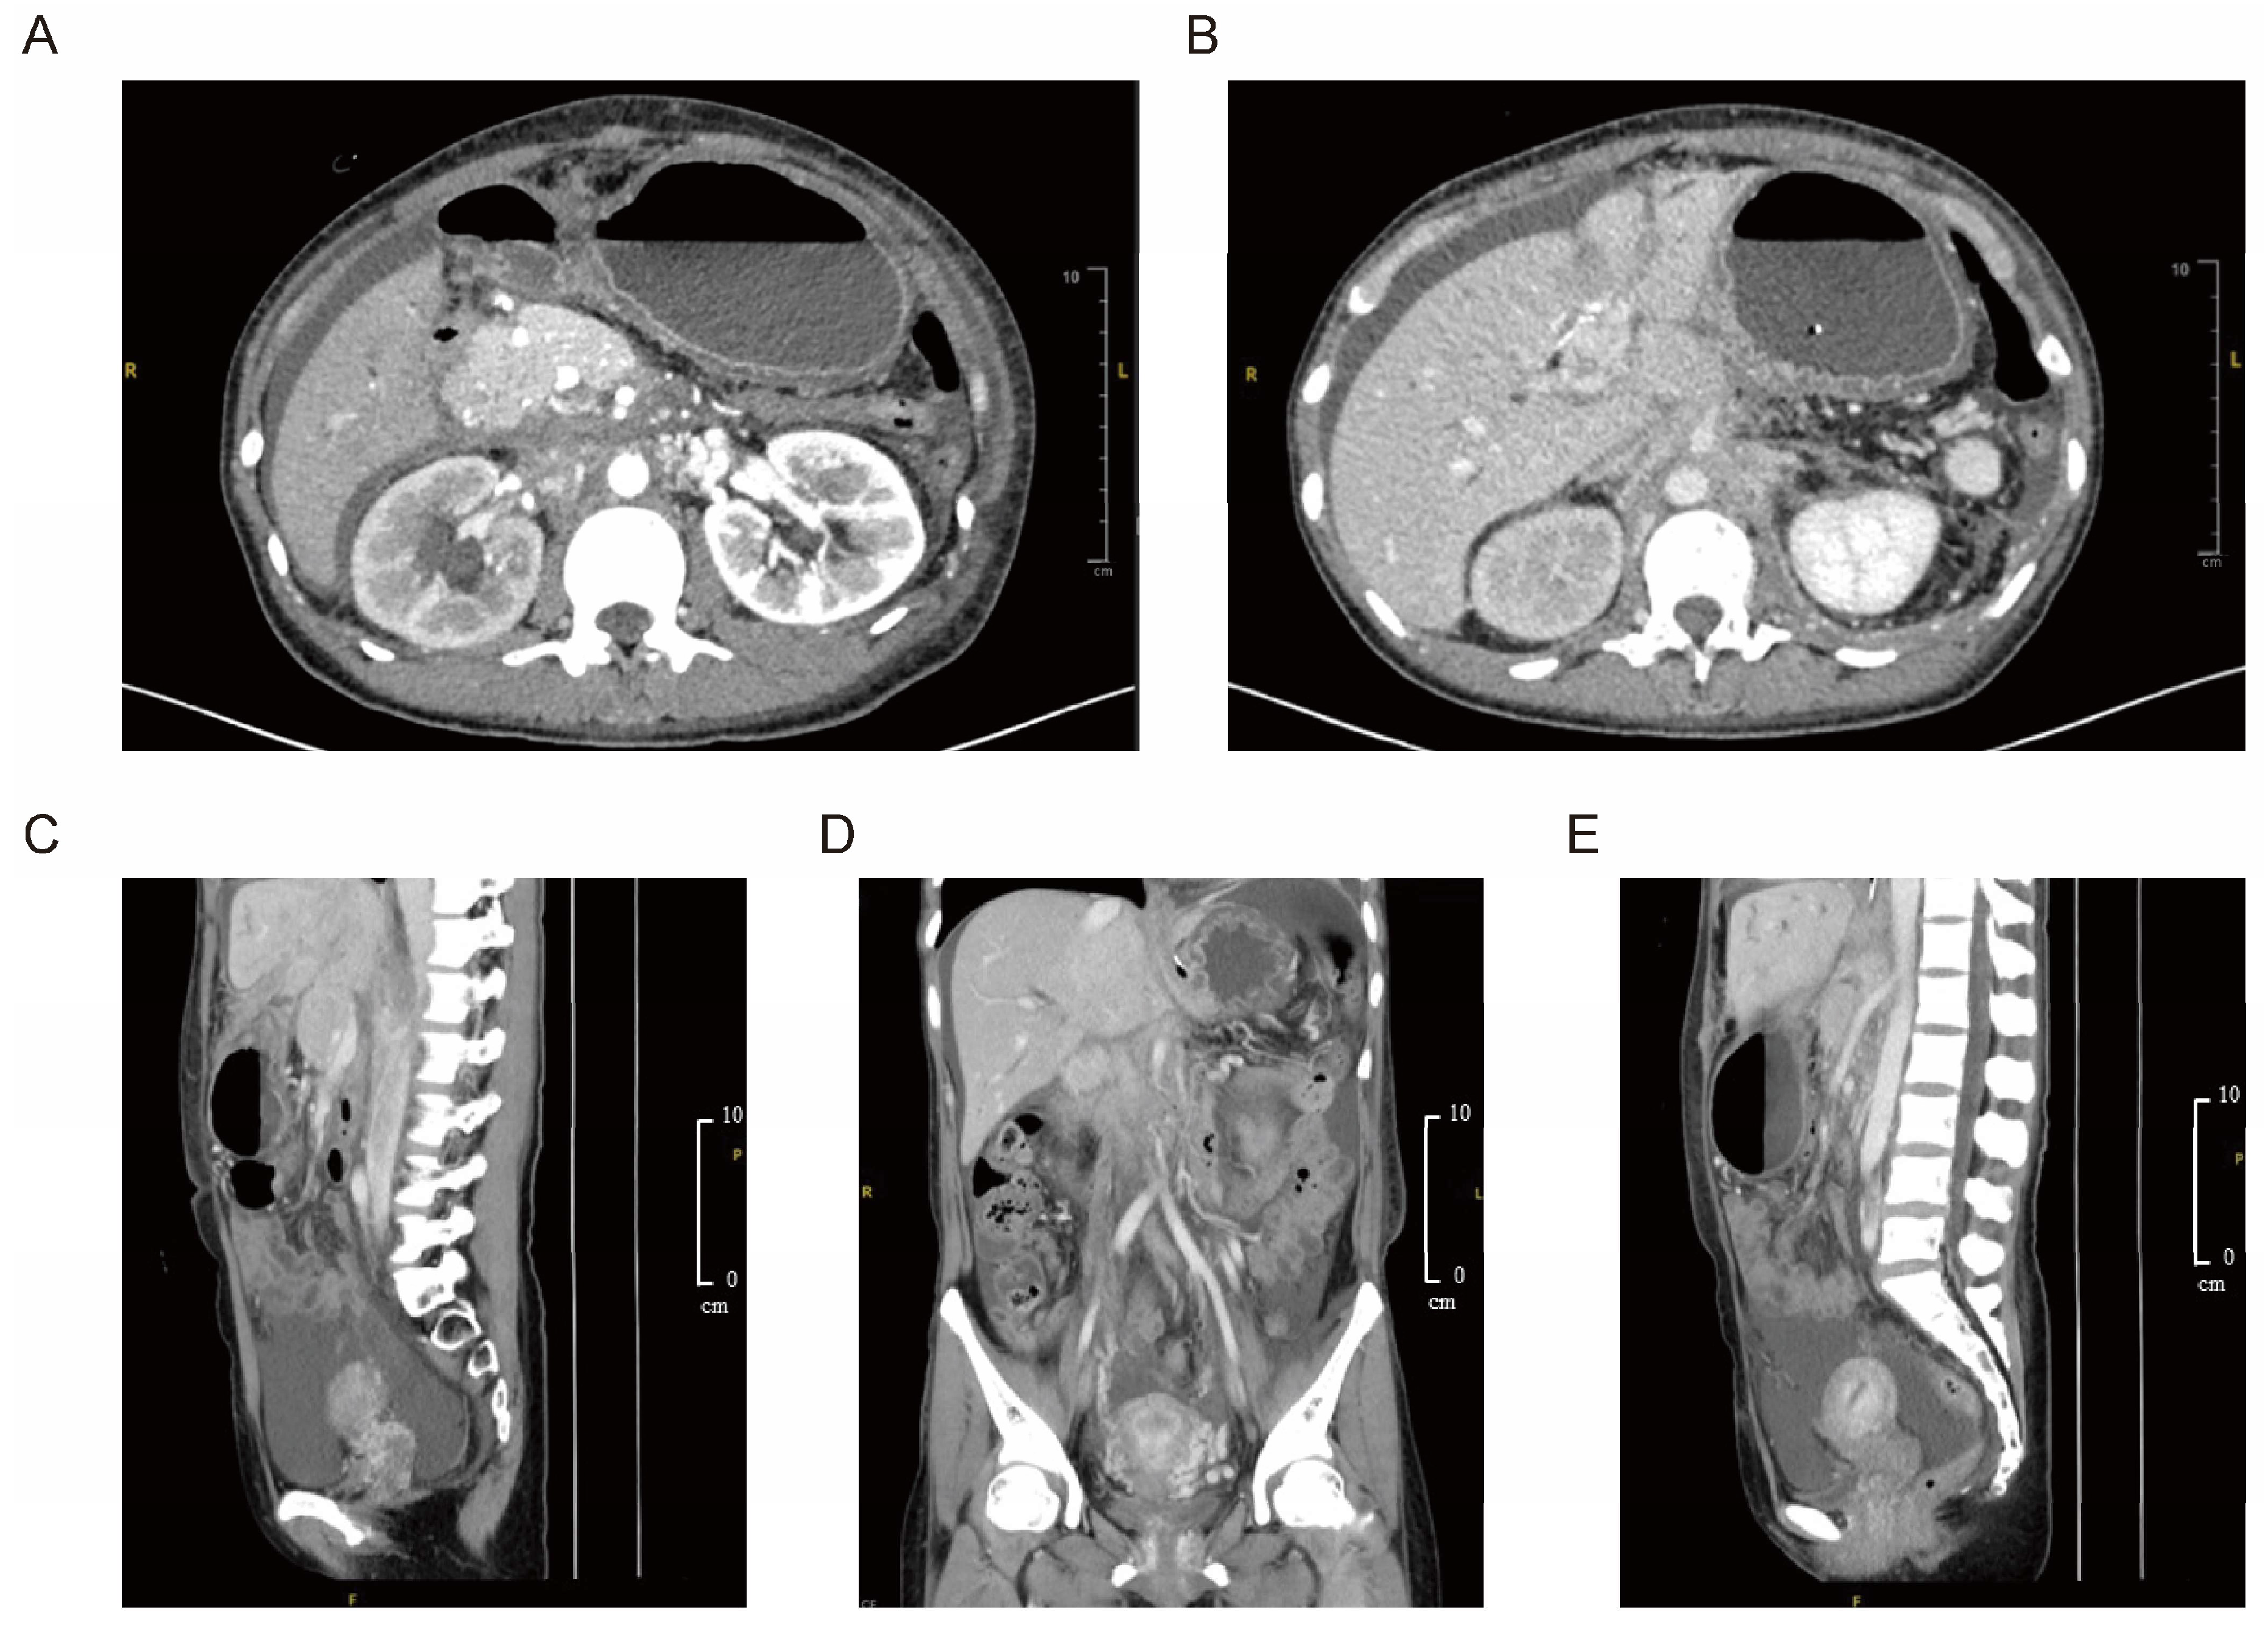

2.2. Radiologic Assessment